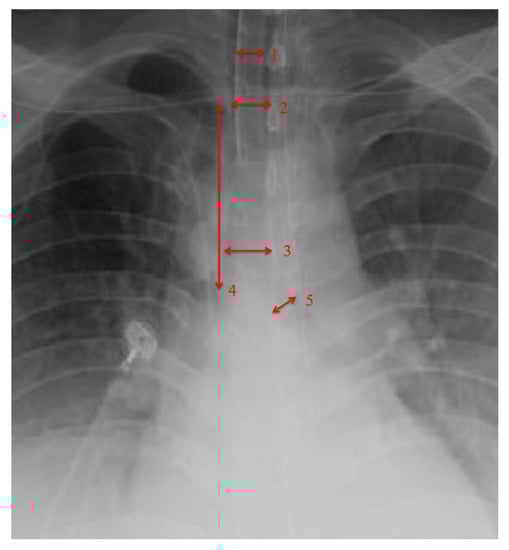

| Tracheal Diameter | 15.75 (±4.03) |

| Intrathoracic Tracheal Length | 82.09 (±20.82) |

| Left main bronchus | 12.765 (±2.85) |

| • Tracheal Diameter Measured at 1st Rib > 15 mm |

| • Tracheal diameter measured at carina > 15 mm |

| • Intrathoracic Tracheal length from 1st rib to carina > 80 mm |

| • Left main-stem bronchus diameter > 10 mm |